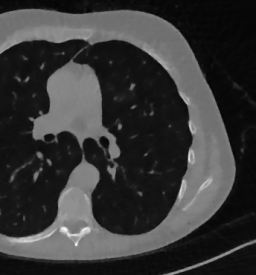

Here we present the results of RISING applied to the Mayo data set introduced in paragraph 4.1. As previously mentioned, we consider two sparse-view CT geometries, namely and . In Figure 4 we report the results for the protocol, achieved on one image of our test set. The top-left image represents the reconstruction. Even if only a small number of iterations are performed, the main structures of the abdomen are visible; however, the image is still blurry. In the image, shown in the upper-right corner, we notice that the TV regularizer has acted to totally eliminate the artifacts and noise, improving the uniformity of the image in the inner structures. When compared to the ground-truth solution in Figure 2, the contours of the details in appear slightly jagged, differently from where they are neat but, usually, corrupted by artifacts. The bottom row of Figure 4 shows the two and images, respectively from left to right. It is evident that has retrieved many details but it presents noisy components, reflecting the features of its target image . Our solution is less corrupted, since the low-contrast regions are correctly preserved and the noise is not visible. These observations are confirmed by Figure 5, which plots the intensity profiles taken over the red line in the second crop (Figure 2). In our approach (on the right) the CNN has accurately learnt the map of (8) and the red profile mostly overlaps the black one. On the contrary, the profile (on the left) is more distant from its target reference.

We now consider the CT protocol whose results are reported in Figure 6.

In this case, the tomographic reconstruction is more challenging than in the previous experiment. The starting image has evident streaking artifacts and blur and some details are lost, especially in the first zoom. The artifacts are reduced in the (top right image), where some details are recovered and the edges are quite neat.

The image obtained with the proposed RISING (bottom right) is visually an excellent reconstruction. It is very similar to the image, whose training, we remark, is based on more informative target images.

In Figure 7 we plot for these experiments, the same profiles of Figure 5.

In the left graph, we analyse the performance of LPP approach: the reconstruction gets values quite close to the GT, but it does not fit well the target black line.

In the right graph, we analyse the performance of RISING approach: the solution almost overlaps the target profile, confirming that the network has correctly learned.

At last we underline that the solutions of the CS regularized model are very similar in case of and geometries.